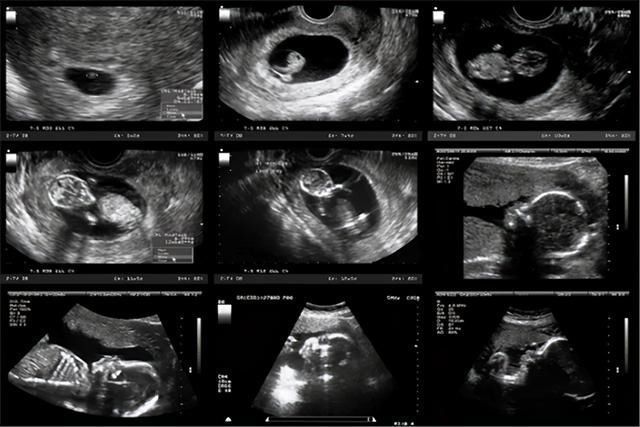

孕妇在生产之前都要经过很多次的产检,而孕晚期的产检主要就是查看胎位正不正、检测胎儿的大小、评估出胎儿的体重,从而来判断孕妈可以采取哪种生产方式进行分娩。

胎位和胎儿大小都是通过做B超测量出来的,而胎儿体重大部分则都是靠有经验的医生,根据B超胎儿大小的数据,以及孕妈的肚形而估算的。

【 产检|宝宝只有6斤,却因产检时医生的误判,导致本想顺产只好选择剖腹】36周的时候,B超显示双顶径89mm,我请医生帮忙预估体重。

她看了看我的肚子说:胎儿已经超重了,现在差不多都有7斤多了,离预产期还有1个月,估计得长到9斤多,如果不控制住肯定不能顺产。